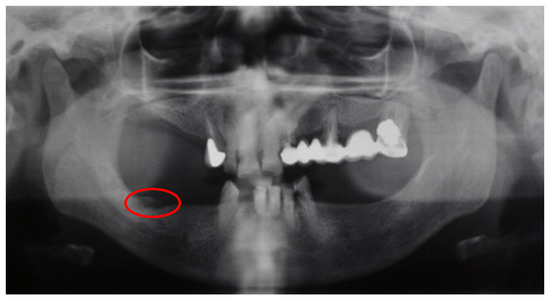

| Patient | Age | MRONJ Stage |

|---|---|---|

| Patient 1 | 44 | I |

| Patient 2 | 79 | II |

| Patient 3 | 61 | II |

| Patient 4 | 69 | I |

| Patient 5 | 85 | III |

| Patient 6 | 77 | I |

| Patient 7 | 65 | I |